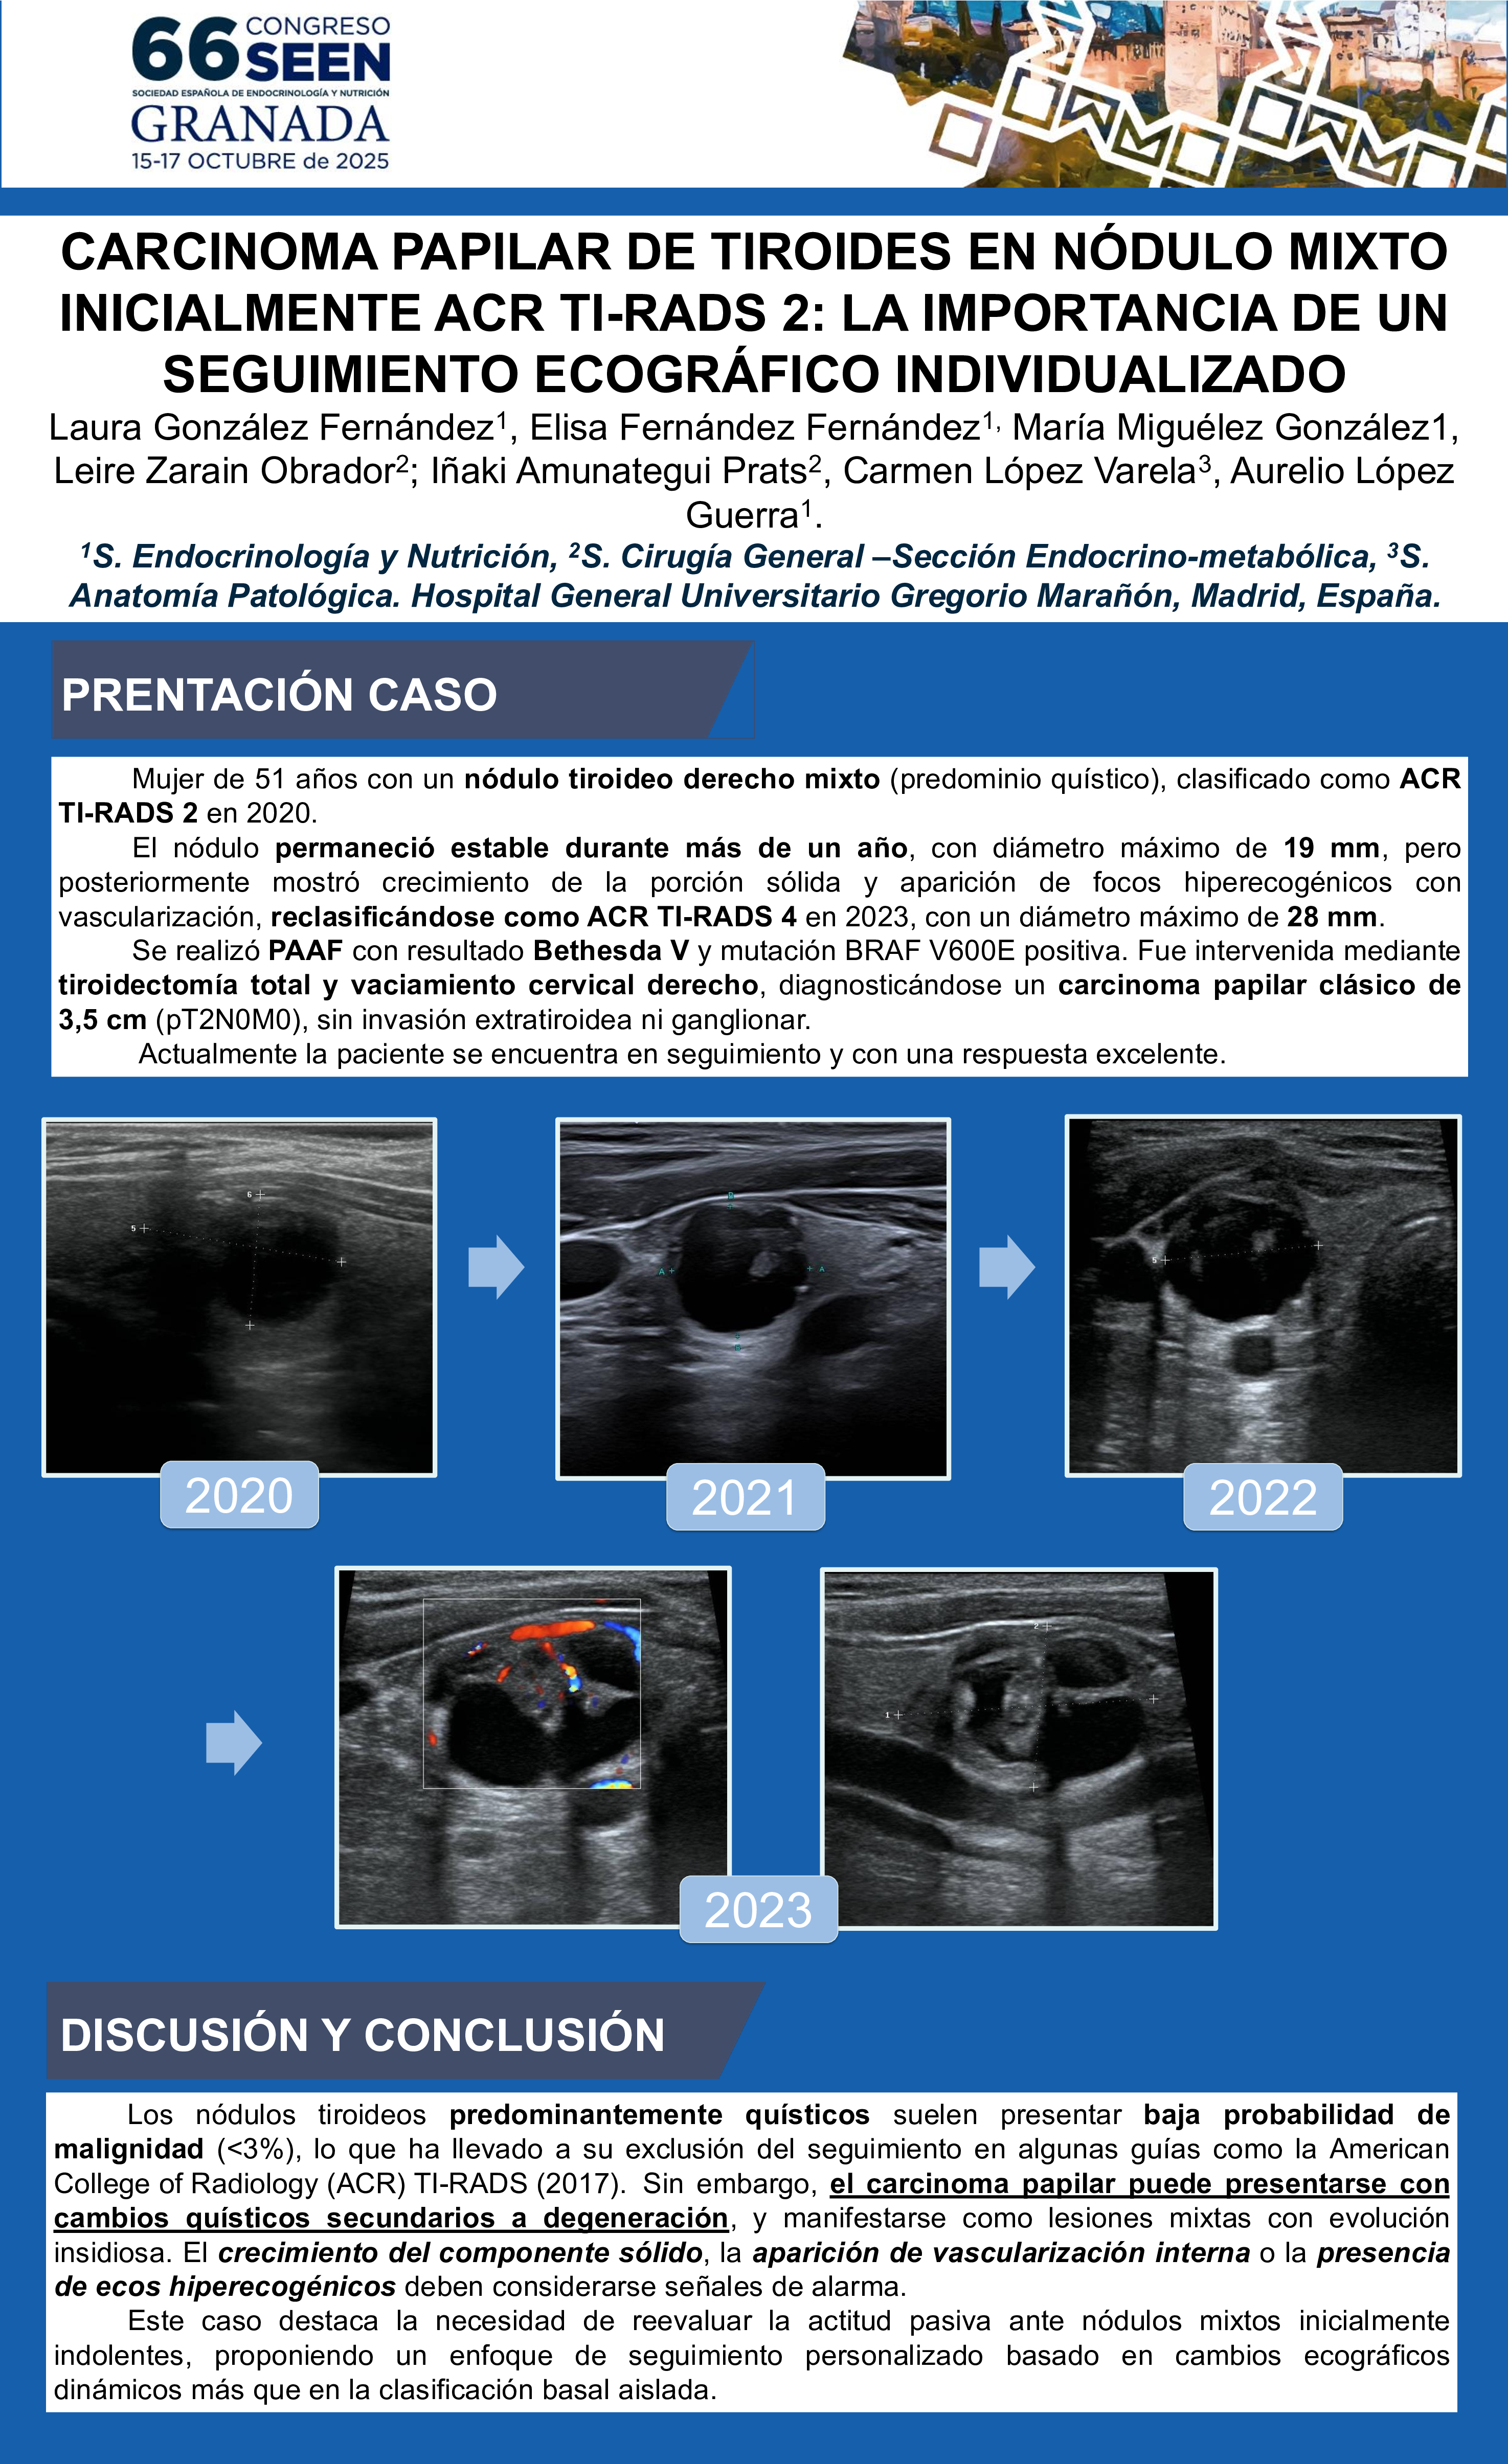

Laura González Fernández; Elisa Fernández Fernández; María Miguélez González; Leire Zarain Obrador; Iñaki Amunategui Prats; Carmen López Varela; Aurelio López Guerra